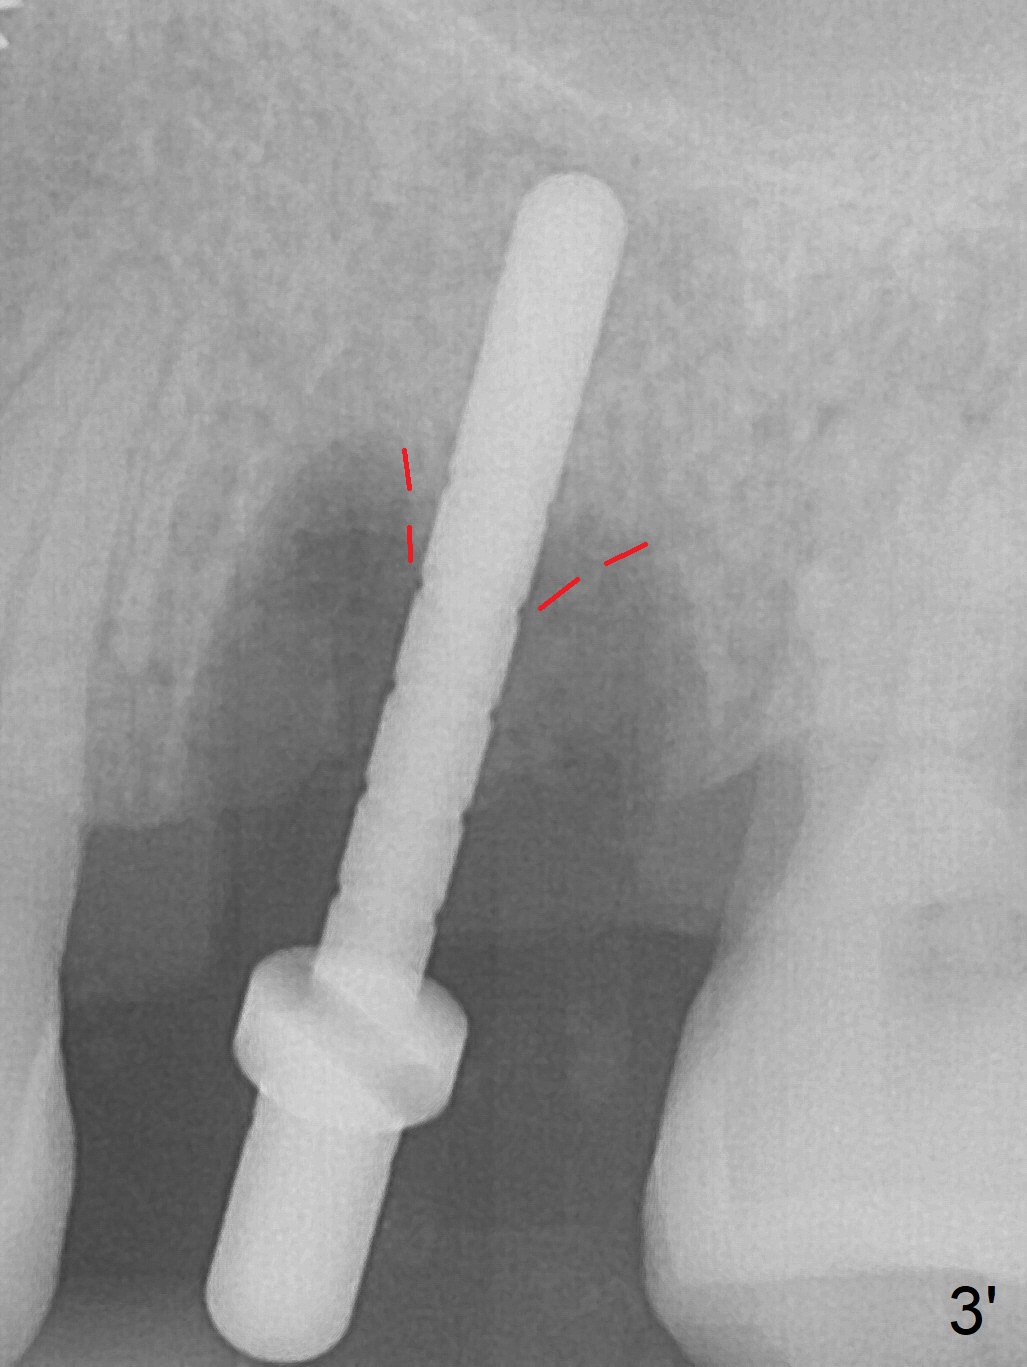

The ridge over the mobile tooth #14 is wide, suggesting bruxism pathogenesis (Fig.1). In spite of calculus over the roots of the extracted tooth (Fig.2), the septum remains. Osteotomy is initiated in the palatal slope of the septum (Fig.3,3' red dashed line). A 4.3 mm Magic Drill (MD) cannot bite into the bone probably because of the slope. Sequential osteotomy has to be done, starting with the smallest MD until 4.8 mm one. A 5x9 mm dummy implant is placed with 50 Ncm (Fig.4). To place 5x11 mm IBS implant (Fig.5), 5.3 mm MD has to be used; prior to implant placement, sinus lift is accomplished with mixture of autogenous bone and Vanilla graft (white *); more allograft (black *) is placed around the implant before insertion of a 6x5.7(3) mm abutment. More allograft is placed around the abutment (Fig.6 *) prior to an immediate provisional fabrication. The grafted bone appears to become the native bone, although at the low density, 6.5 months postop (Fig.7). The implant at #14 appears to have been placed in the middle of the alveolus buccopalatally (Fig.8).